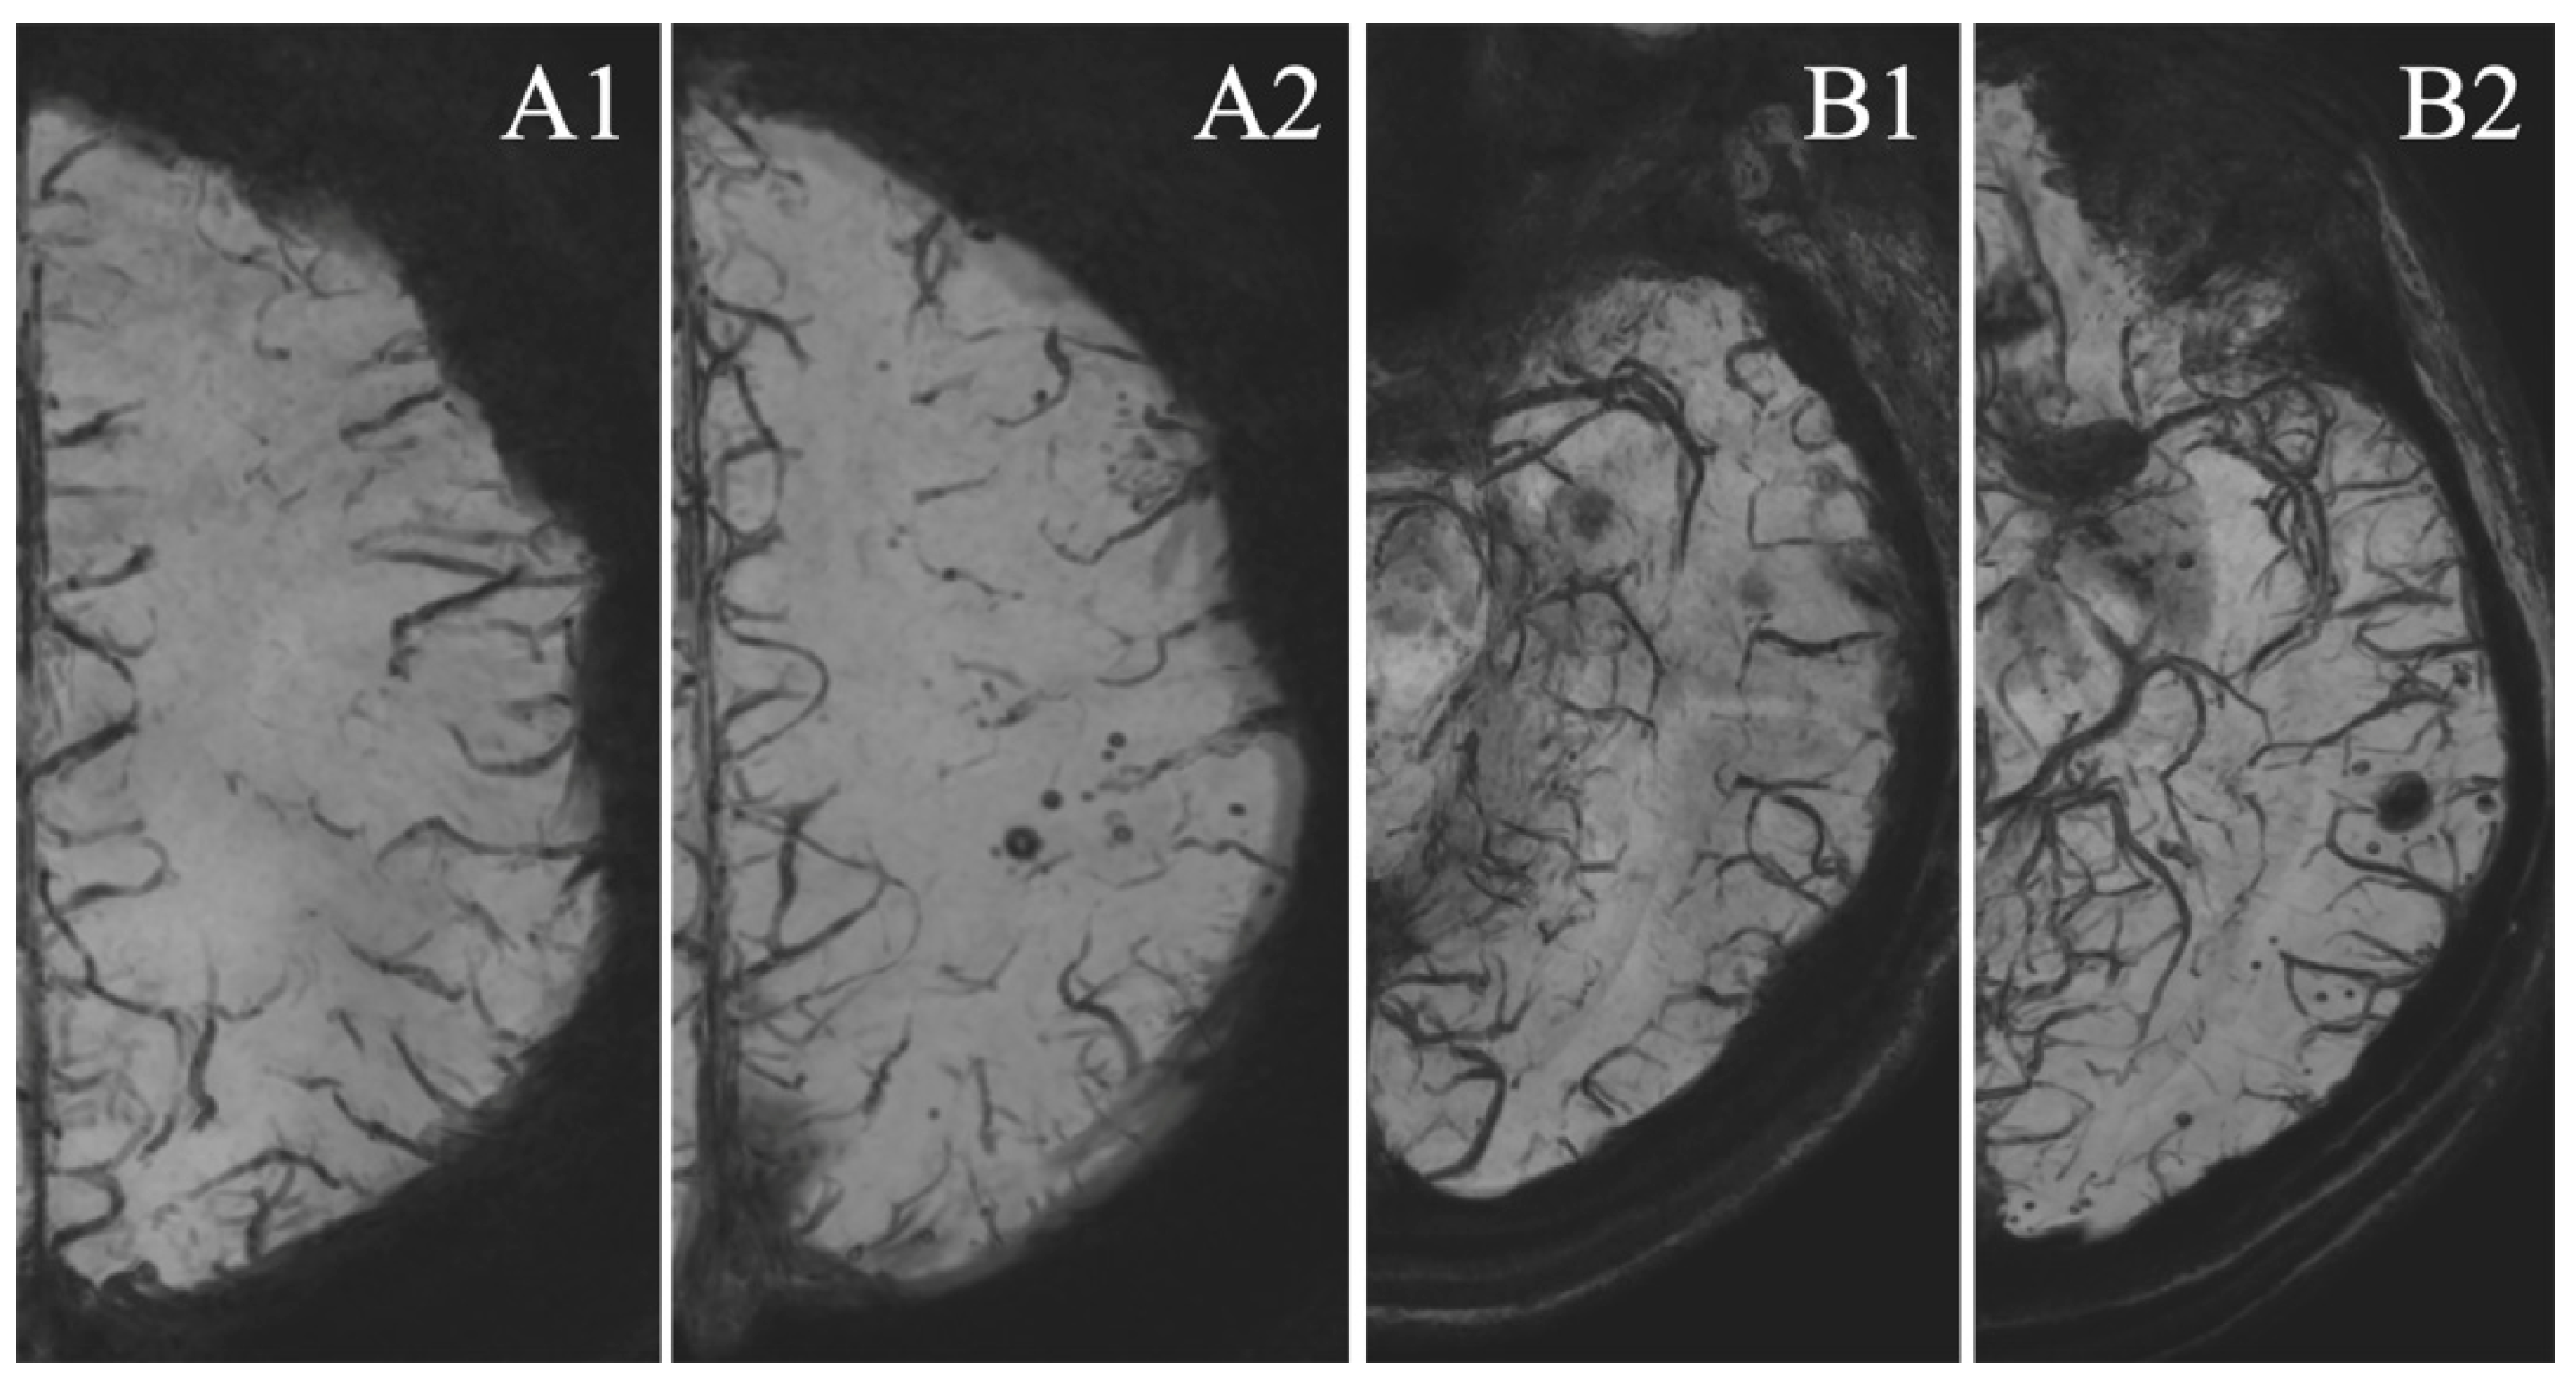

3.4. MSA Analysis